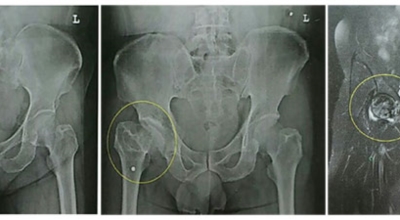

고관절염은 고관절에 발생하는 관절염을 말하며 고관절의 연골이 닳게 되면서 뼈와 뼈가 서로 부딪히며 통증을 유발하게 됩니다. 고관절염 초기 증상으로는 사타구니 부위가 불편하게 느껴지며, 무리하면 통증이 발생할 수 있고 관절염 증상이 악화되면서 사타구니에서 느끼던 통증이 허벅지와 엉덩이 통증으로 이어지기도 하는데요 고관절염 통증 증상으로 초기에는 허리 통증이 나타나 허리 질환과 혼동하기 쉬우며 특히 척추질환이 있는 사람은 고관절 통증 증상과 마찬가지로 엉덩이, 다리 통증이 동반되기 때문에 더욱 헷갈리는 경우가 많다고 합니다.

나이가 들면 흔히 생기는 질환 중 하나입니다. 관절을 보호하고 있는 연골의 손상이나 퇴행성 변화로 인해 관절을 이루는 뼈와 인대 등에 손상이 생겨 염증과 통증이 발생하는 질환입니다. 고관절 쪽 연골이 닳게 되면서 망가지게 되고 또 쉽게 없어지지 않는 통증에 시달릴 수 있습니다.